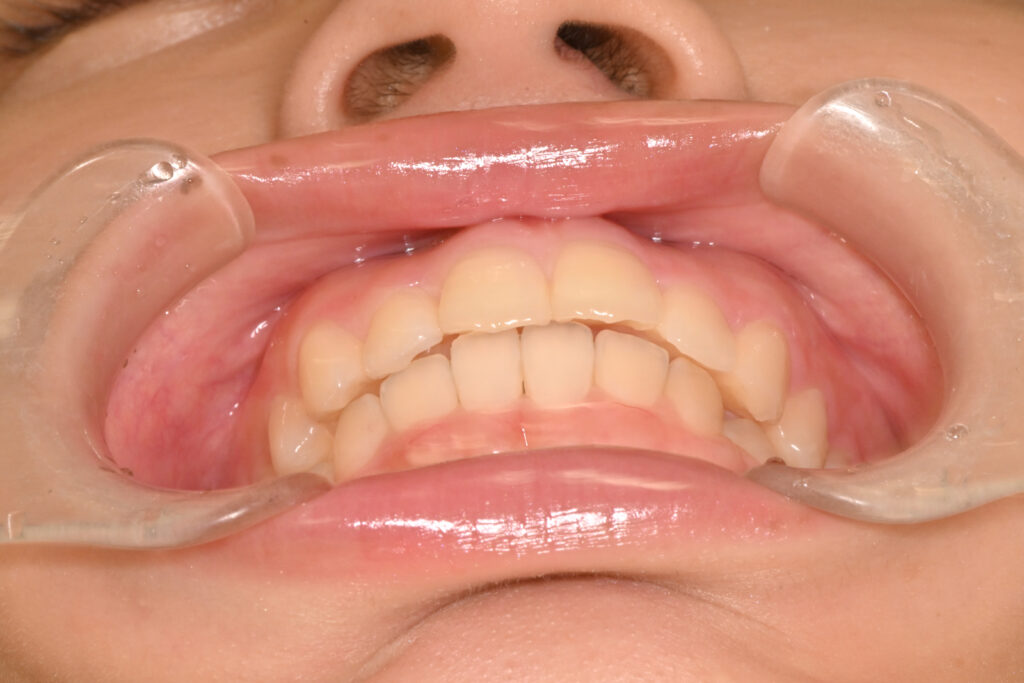

正面

治療前

治療後